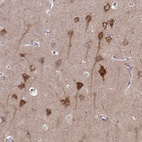

Anti-ASAP1 Antibody

Polyclonal Antibody against HUMAN ASAP1